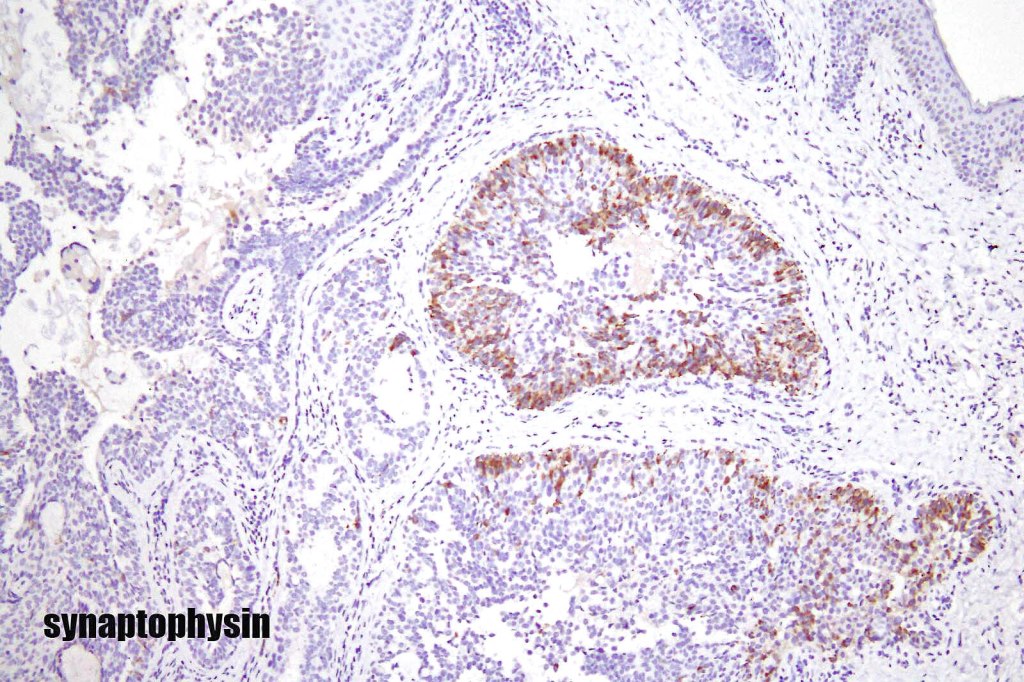

•In a subset of tumors, neuroendocrine markers- synaptophysin, chromogranin & NSE +ve (neuroendocrine subtype)

. EMPSGCa shares this IHC profile